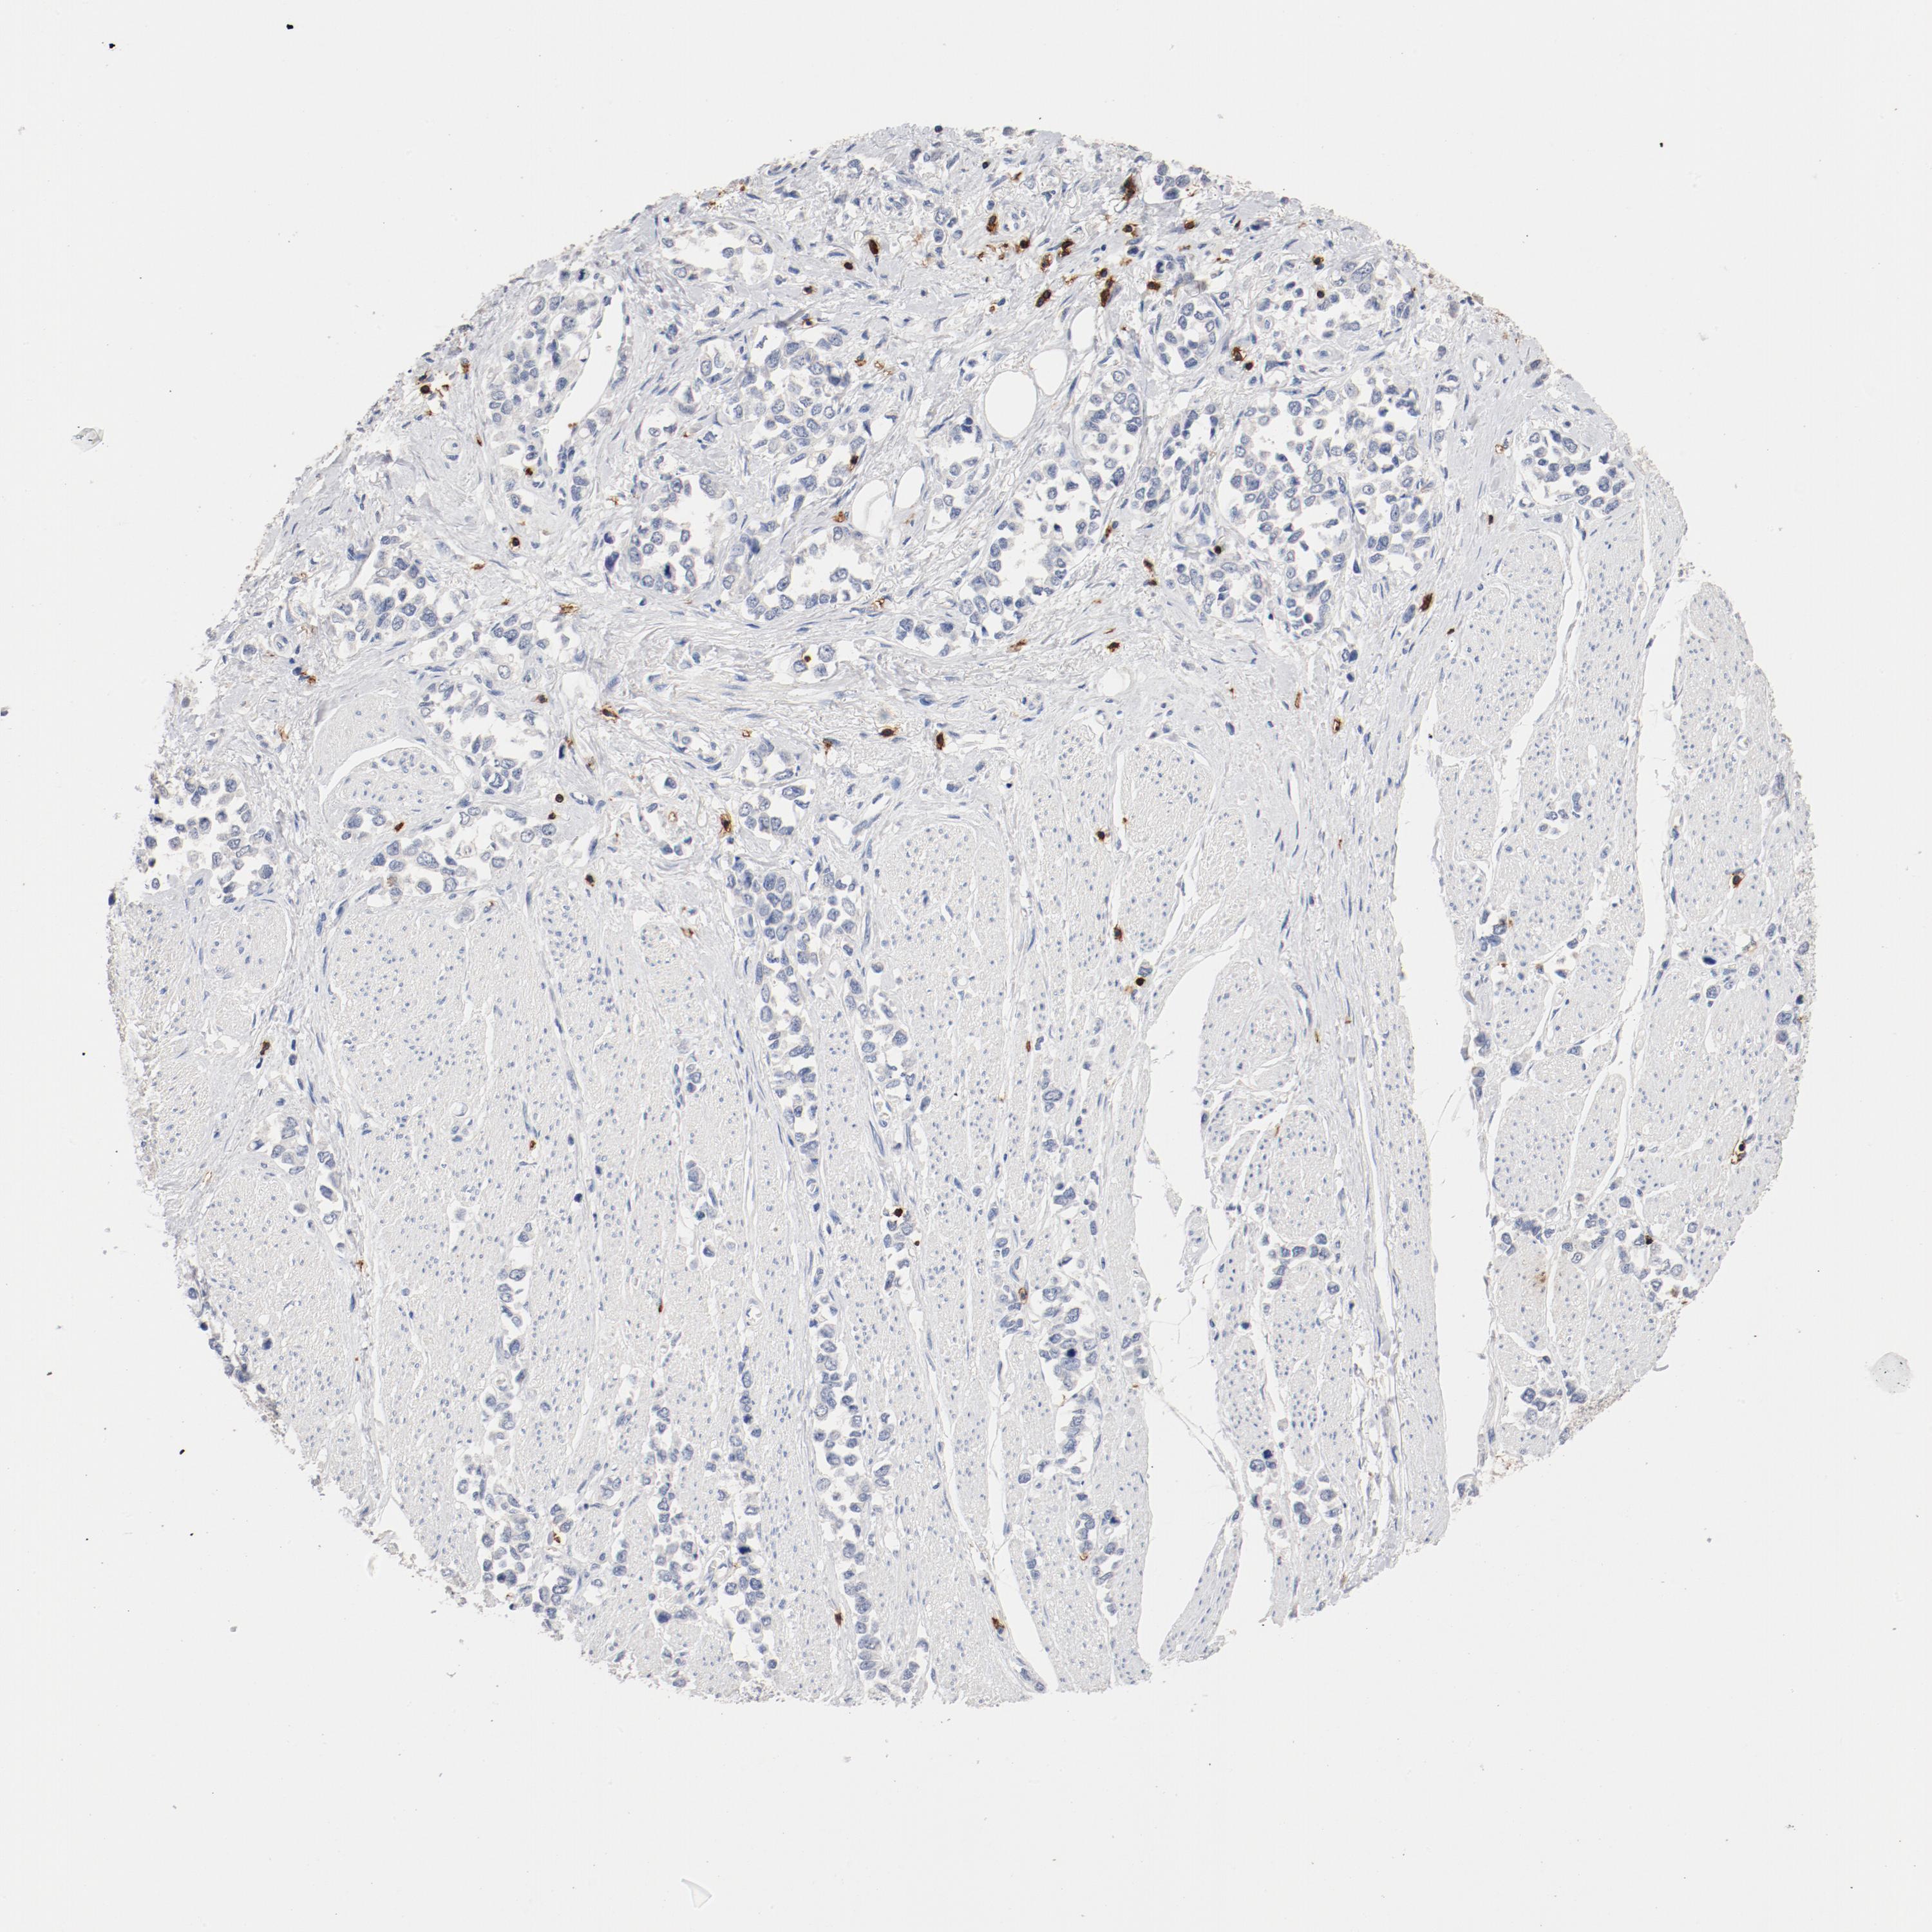

STOMACH CANCER - Protein expressioni

A mouse-over function shows sample information and annotation data. Click on an image to view it in a full screen mode. Samples can be filtered based on level of antibody staining by selecting one or several of the following categories: high, medium, low and not detected. The assay and annotation is described here.

Note that samples used for immunohistochemistry by the Human Protein Atlas do not correspond to samples in the TCGA dataset.

Antibody stainingi

Antibody staining in the annotated cell types in the current human tissue is reported as not detected, low, medium, or high, based on conventional immunohistochemistry profiling in selected tissues. This score is based on the combination of the staining intensity and fraction of stained cells.

Each image is clickable and will lead to virtual microscopy that enables deeper exploration of all samples and also displays staining intensity scores, fraction scores and subcellular localization as well as patient and tissue information for each sample.

Antibody HPA008750

Antibody CAB004651

Staining

High

Medium

Low

Not detected

Intensity

Strong

Moderate

Weak

Negative

Quantity

>75%

75%-25%

<25%

None

Location

Nuclear

Cytoplasmic/membranous

Cytoplasmic/membranous,nuclear

Adenocarcinoma, NOS

Adenocarcinoma, High grade